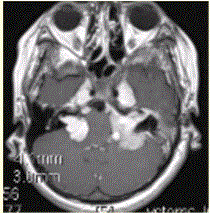

女性,15岁。MR表现如下图,可能的诊断是A.神经纤维瘤病I型B.神经纤维瘤病II型C.结节性硬化D.双侧听神经瘤E.颜面血管瘤综合征

问题 女性,15岁。MR表现如下图,可能的诊断是

选项 A.神经纤维瘤病I型 B.神经纤维瘤病II型 C.结节性硬化 D.双侧听神经瘤 E.颜面血管瘤综合征

答案 B